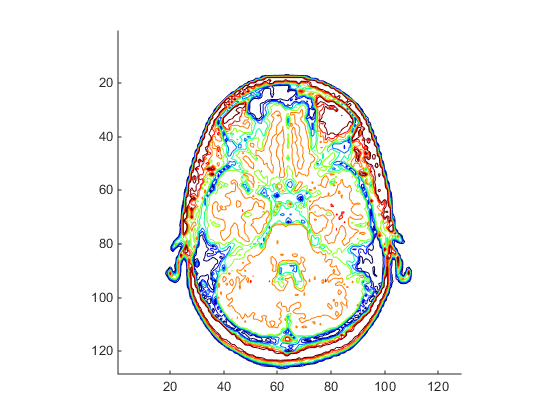

Displaying a 2-D Contour Slice

Visualize MRI data as a volume data because it is a collection of slices taken

progressively through the 3-D object. Use contourslice to display a

contour plot of a volume slice. Create a contour plot with the same orientation

and size as the image created in the first part of this example:

To improve the visibility of details, this contour plot uses the

jet colormap. The brighten function reduces the

brightness of the color values.

cm = brighten(jet(length(map)),-.5); figure colormap(cm) contourslice(D,[],[],image_num) axis ij xlim(x) ylim(y) daspect([1,1,1])